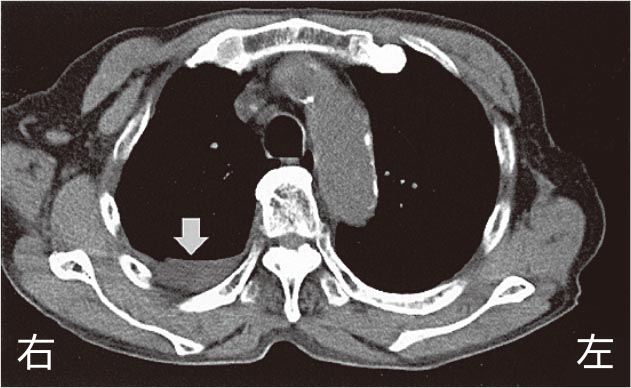

胸部CTを下に示す.

矢印の所見はどれか.

- 1.肺 炎

- 2.胸 水

- 3.肺 癌

- 4.肺塞栓

- 5.心囊液貯留

解答: 2